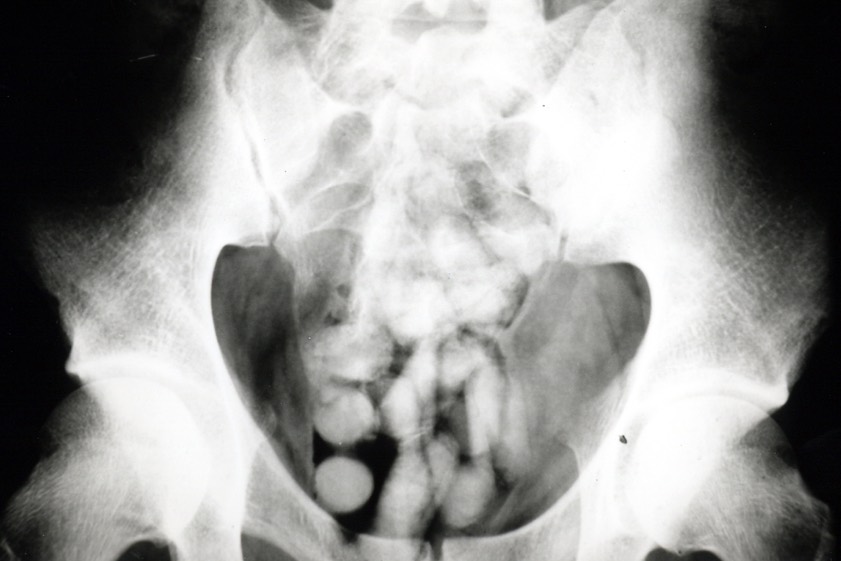

"Das Röntgenbild bestätigte den Verdacht der Zöllner. Im Laufe des Tages kamen 95 Behältnisse mit Kokain zum Vorschein, die über den natürlichen Weg ausgeschieden wurden", berichtet Marie Müller, die Pressesprecherin des Hauptzollamts München.

Insgesamt konnte rund ein Kilogramm Kokain sichergestellt werden. Gegen den Mann wurde auf Antrag der Staatsanwaltschaft Landshut durch das Amtsgericht ein Haftbefehl erlassen. Die weiteren Ermittlungen in diesem Fall hat das Zollfahndungsamt München übernommen.